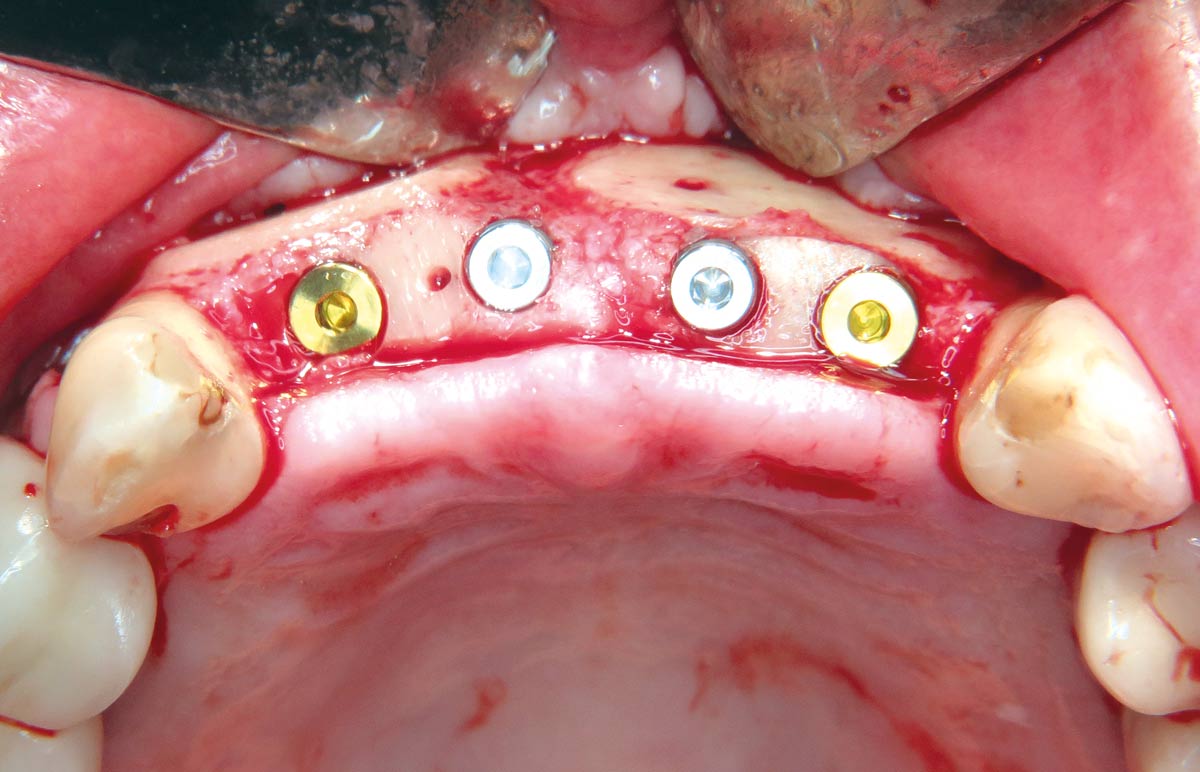

18 / 22 - Stable implantation into the augmented bone